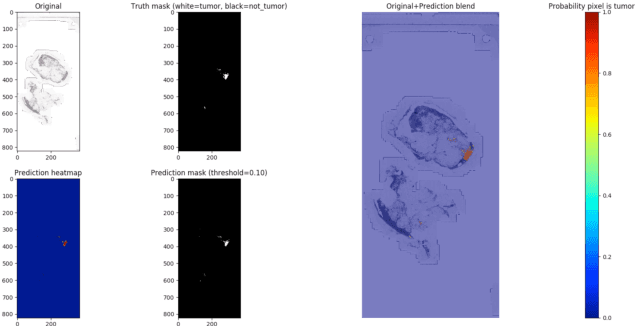

Detection and Classification of Breast Cancer Metastates Based on U-Net

Sep 09, 2019

This paper presents U-net based breast cancer metastases detection and classification in lymph nodes, as well as patient-level classification based on metastases detection. The whole pipeline can be divided into five steps: preprocessing and data argumentation, patch-based segmentation, post processing, slide-level classification, and patient-level classification. In order to reduce overfitting and speedup convergence, we applied batch normalization and dropout into U-Net. The final Kappa score reaches 0.902 on training data.